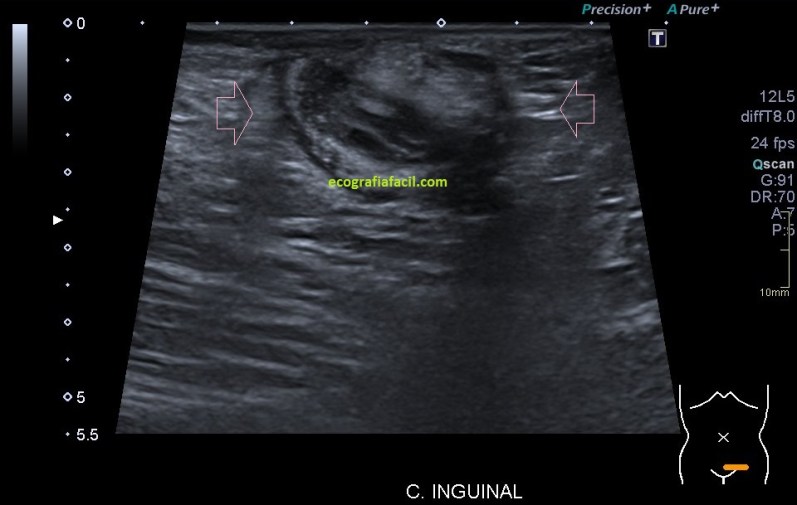

Toca ahora después de la localización y estudio, las medidas que arrojaban una lesión bastante grande.

Ahora, una de las piezas claves de este puzzle, que es la vascularización, sabemos que el lipoma no posee vascularización, en este caso, la lesión sí que tiene una vascularización, no demasiado evidente, pero demostrada y por tanto, siempre una línea roja en el estudio de los lipomas.

La lesión era bastante grande , ocupaba como ves en la imagen una parte importe del canal inguinal también en la imagen 7.

Se completa estudio con Ct ante las características de la lesión y la imagen que tenemos, muy llamativa, refrenda la presencia de una lesión en el canal inguinal que posee una gran calcificación.  En el CT se objetiva, imagen 7, una afectación ligeramente mayor a la estimada en el estudio ecográfico. La sospecha para la radióloga fue de lesión primaria de cordón inguinal compatible con Liposarcoma, a tenor de todos lo hallazgos en las dos pruebas, basándose principalmente en la heterogenicidad de la imagen, la calcificación y el comportamiento no compatible con hernia inguinal ni con la semiología típica del lipoma.